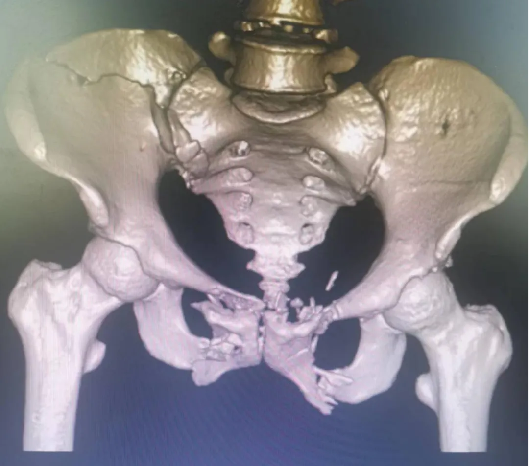

患者黃(huáng)某,因車禍外傷導致全身多處疼痛入院(yuàn),入院即因失血性休(xiū)克於ICU監(jiān)護,完善檢查顯示雙側恥骨粉碎性骨折、右側髂骨多處骨折、右骶髂關節脫位,提示骨盆前-後環均不穩定(dìng)。

對於此種前後環均嚴重失穩(wěn)的複雜(zá)骨盆(pén)骨折的治療,保守治療不僅需長期臥床,易導致褥(rù)瘡、肺部感染、泌尿(niào)係(xì)感染及深靜脈血栓風險,同時勢必影響後(hòu)期功(gōng)能恢複,嚴重降低患者未來生活質量。傳統開放術式手術切口大、手(shǒu)術時間長,手術難度極大,同時存在盆腔內血管神經及膀胱的醫源性損傷風險,以往,遇到此種嚴重(chóng)病情隻能依賴上級醫院專家來(lái)院手術指導,但基於(yú)近期成功開展的骨盆微創治療的經驗支持,外一科董(dǒng)明主任反複(fù)研究患者病情及影像,充(chōng)分(fèn)考慮手術創傷與(yǔ)風險後,決定開展(zhǎn)骨盆骨折(shé)有限切開複位(wèi)內固定術。